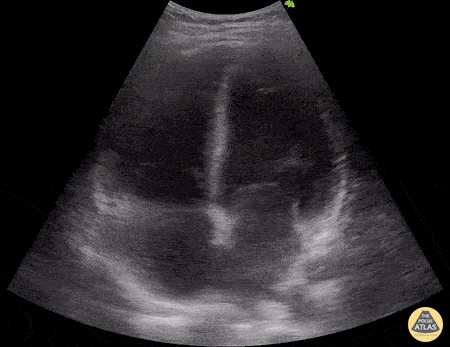

A patient with cough, dyspnea, and mild edema. POCUS shows following on both lungs. Most likely diagnosis?

Findings: B lines, thin smooth pleura

Diagnosis: What is CHF / cardiogenic pulmonary edema?